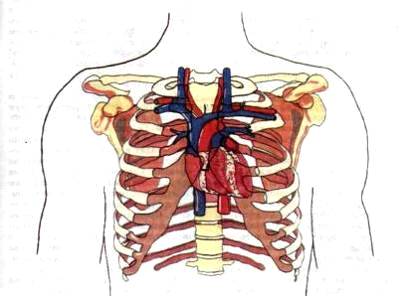

Анатомия Сердца: Расположение и Функции